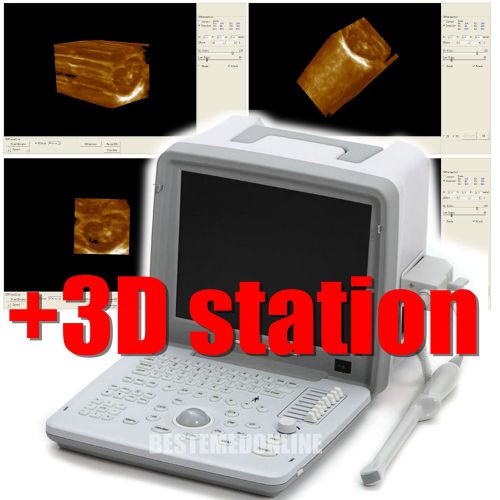

Built_in 3D Ultrasound Machine Scanner(Brand_New! Portable PC_platform)+ LINEAR

NEW 3D PC platform Ultrasound Scanner w 3.5MHz CONVEX probe print via laser

3D Laptop Digital Ultrasound machine Scanner 5.0 Mhz Micro-convex 3D workstation

CE FUll Digital +3D Laptop Ultrasound Scanner+** Convex probes and linear probe

100% Warranty 3D Digital Ultrasound Machine Scanner Systerm With Convex probe CE